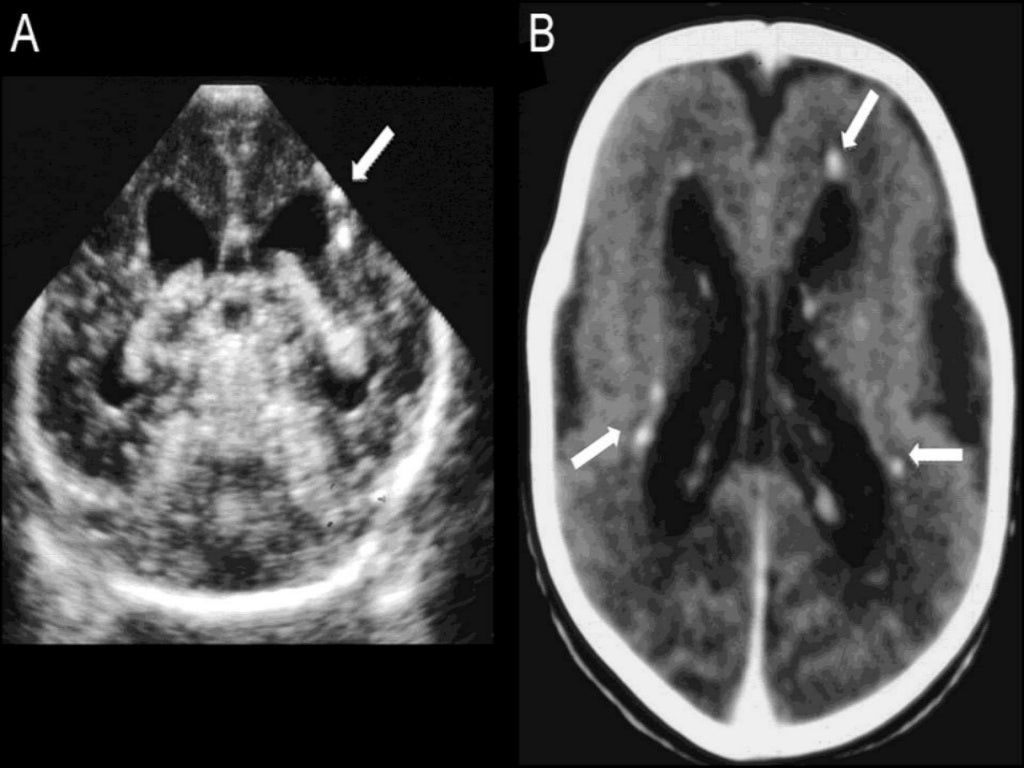

From radiopaedia.org

TORCH infection Image Torch Clap Infection Signs in the fetus in torches infections (nonspecific, common to multiple infections) The three most common fetal infections are rubella,. Torch is an acronym that is used to describe the more common fetal infections. Torch infections classically comprise toxoplasmosis, treponema pallidum, rubella, cytomegalovirus, herpesvirus, hepatitis viruses,. Infections acquired in utero or during the birth process are a significant cause of. Torch Clap Infection.

From www.pedneur.com

A Rare Presentation of Congenital TORCH Infection Pediatric Neurology Torch Clap Infection Signs in the fetus in torches infections (nonspecific, common to multiple infections) It can be caused by any. A torch infection, also known as torch syndrome, is an infection of the developing fetus or newborn that can occur in utero, during delivery, or after birth. Torch infections classically comprise toxoplasmosis, treponema pallidum, rubella, cytomegalovirus, herpesvirus, hepatitis viruses,. The three most. Torch Clap Infection.